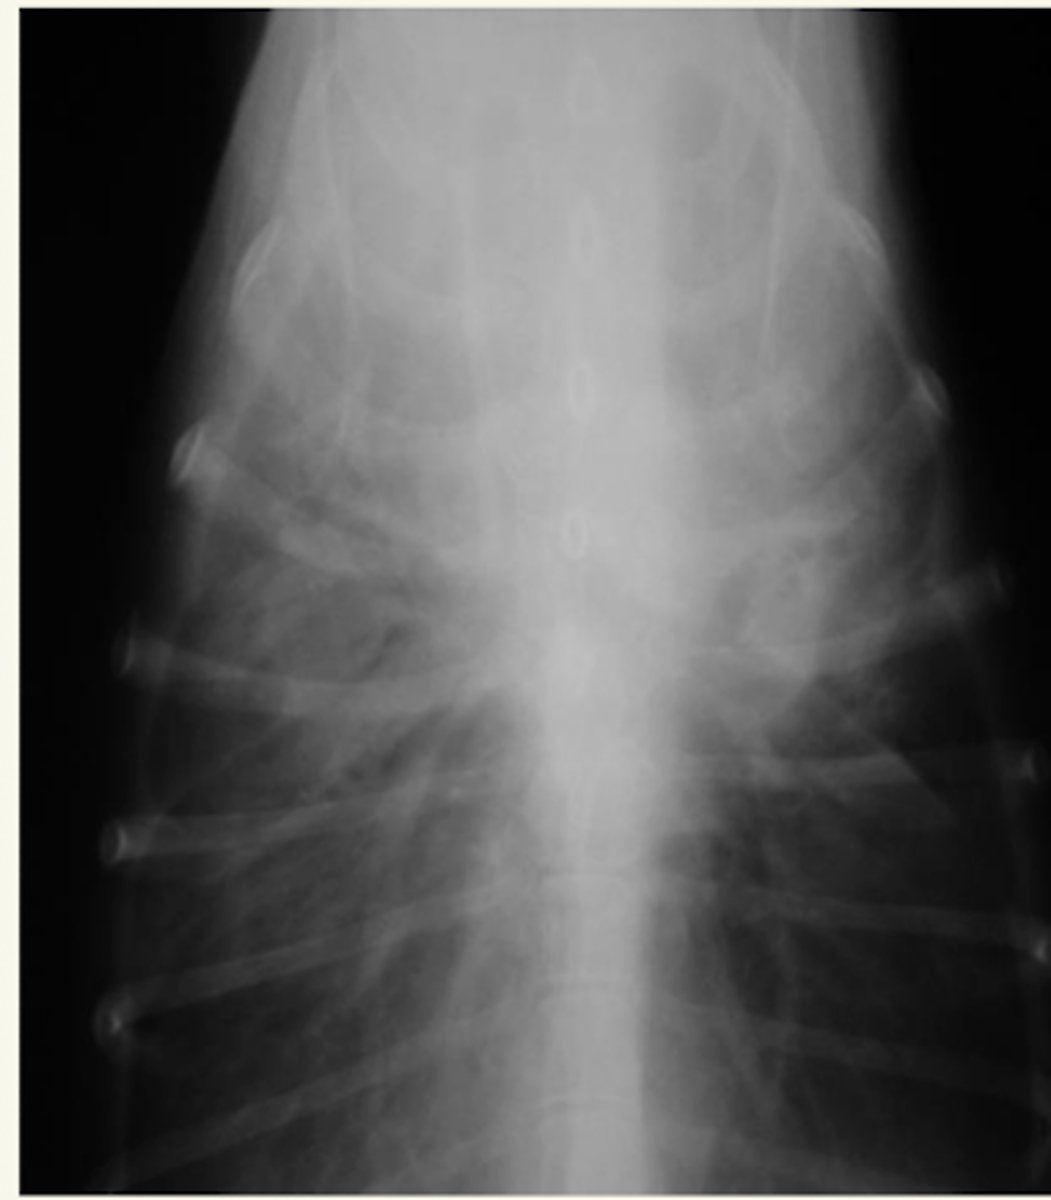

efusión pleural

patología: